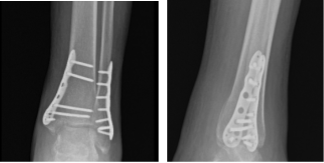

By this time advised the patient to do the R.I.C.E Practice (Rest, Ice, Compression, and Elevation). Left ankle X Ray were reviewed and monitored for 32 weeks post-operative, it showed surgically treated fractures of the distal fibula and medial malleolus.

Left Ankle X-ray complete 3 or more views 1 week post operative

Left Ankle X-ray complete 3 or more views-4 week post operative

Left Ankle X-ray complete 3 or more views 8 weeks post operative

Left Ankle X-ray complete 3 or more views 16 weeks post operative

Left Ankle X-ray complete 3 or more views 8 months post operative

For further review of ankle condition, we agreed to take CT. Result showed healed Tri malleolar fracture status post ORIF with plate and screws in the fibula and the medial malleolus with mild deformity with 1 mm step off at the articular surface in the tibial plafond medially.

CT-Left ankle non-contrast